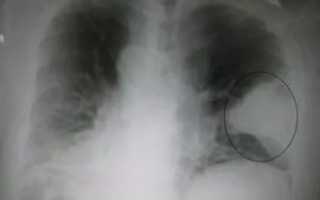

К примеру, абсцесс на снимках просматривается как наличие полостей с нечётким округлым контуром. Также можно просматривать несколько или один очаг воспаления.

Рентгенодиагностика пневмоний проводится и с той целью, чтобы предотвратить серьёзные осложнения. При любом виде данного заболевания пациент может столкнуться со следующими проблемами:

• острая дыхательная недостаточность;

• обструктивный синдром;

• инфекционно-токсический шок;

• острая сердечно-лёгочная недостаточность;

• анемия;

• абсцесс;

• миокардит;

• менингит;

• гломерулонефрит;

• психозы и пр.